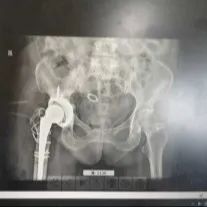

01髋臼和转子间有着大量的骨溶解,需要重新进行植骨处理,同时免造成骨折。

02对股骨柄假体进行了截骨处理。

03髋臼外杯已经穿透进入盆腔中,在处理过程中稍有不慎便会导致肠道等脏器以及血管的损害

最终,经过长达6个时15分的鏖战,手术取得圆满成功,经术后康复训练,鞠婆婆如今已能自由行走,康复出院。